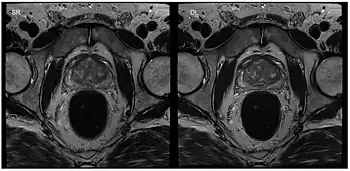

Apart from cardiac MRI other real-time applications deal with functional studies of joint kinetics (e.g., temporomandibular joint,[30] knee and the wrist[31]) or address the coordinated dynamics of the articulators such as lips, tongue, soft palate and vocal folds during speaking (articulatory phonetics)[32] or swallowing.[33] Musculoskeletal imaging in particular benefits from real-time observation. Researchers at the NYU Grossman School of Medicine[34] developed a RT-MRI glove for imaging movement of the hand. The glove uses high impedance coils to prevent the generation of eddy currents from rapidly changing magnetic fields and bSSFP for rapid imaging times. High-impedance coils remove the need for specific coil conformations and active gradient shielding.[35]